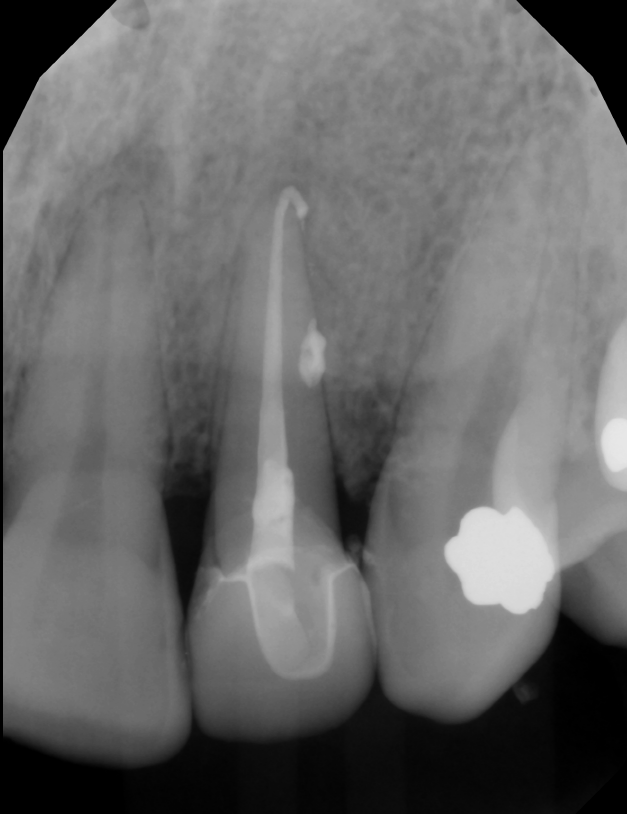

E-Max Crown #10

A 61-year-old male presented following completion of root canal therapy on tooth #10 requiring definitive coronal restoration. An all-ceramic E-max crown was selected to provide optimal esthetics and strength within the anterior region.

Tooth preparation was completed with attention to proper reduction and margin design to support both structural durability and natural translucency. Final impressions were obtained and laboratory communication emphasized shade integration with adjacent dentition to ensure a harmonious result.

At delivery, the restoration demonstrated appropriate marginal fit, esthetics, and occlusal function. Minor chairside adjustments were performed to refine occlusion and ensure patient comfort. The final outcome restored both function and appearance, with the patient reporting satisfaction with the esthetic result.